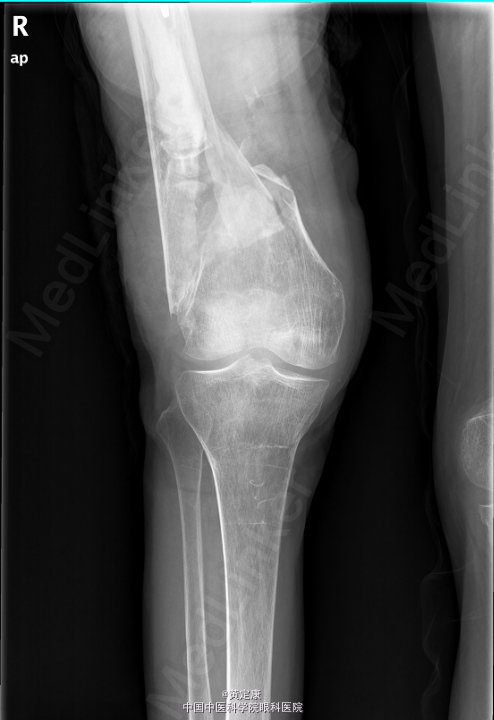

患者,女,82岁,因“摔伤致右下肢疼痛伴功能受限1天”入院。 患者1天前因外伤致右下肢剧烈疼痛,无法行走,。送至外院急诊,X线示“右股骨髁上骨折”,拟“右股骨髁上骨折”收治入院。

右膝部肿胀,膝关节活动受限,右足各趾活动感觉正常,末梢血运正常。石膏固定。检查提示:右股骨髁上骨折。

初步诊断: 右股骨髁上骨折 行[右]股骨骨折切开复位钢板内固定术